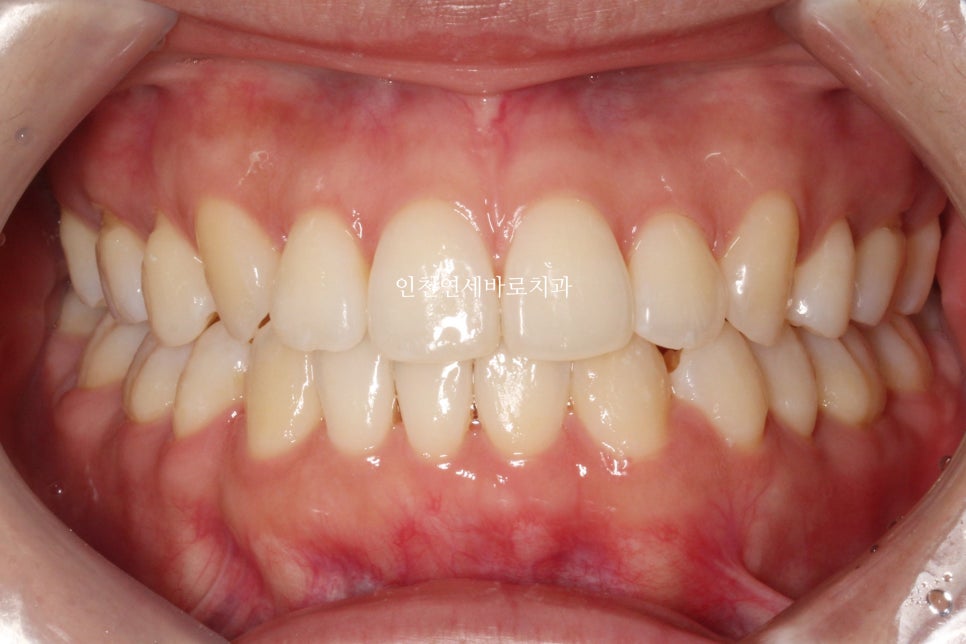

지난 주 마무리된 모습

결손치아가 있지만 교합은 문제없게 마무리

그리고 중요한 앞모습

과정이야 힘들고 오래걸리고 장치도 교체하고 어려웠지만

목표한바는 모두 달성한 치료입니다.